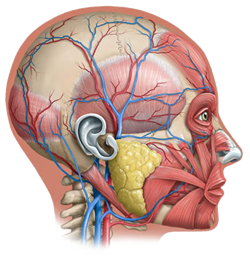

If "a picture paints a thousand words" and using visuals with text increases retention, then Precision Graphics has immeasurably enhanced

the art and science of learning. Sneak a peek under the covers of textbook illustration and

design with Precision Graphics' Jan Troutt (Vice President of Publishing Services) and Heidi Richter (Certified

Medical Illustrator and Senior Illustrator) as they highlight the successes and challenges that they've faced in an ever-changing world of illustration, design and animation.

If "a picture paints a thousand words" and using visuals with text increases retention, then Precision Graphics has immeasurably enhanced

the art and science of learning. Sneak a peek under the covers of textbook illustration and

design with Precision Graphics' Jan Troutt (Vice President of Publishing Services) and Heidi Richter (Certified

Medical Illustrator and Senior Illustrator) as they highlight the successes and challenges that they've faced in an ever-changing world of illustration, design and animation.

Founded in 1977 by Jeff Mellander, Precision Graphics is the largest educational textbook illustration

studio in the United States today. Jan Troutt, a Precision Graphics mainstay for over 24 years, has seen the

transition from one-color line drawings to today’s highly illustrated, full-color textbooks and media projects.

Heidi Richter has melded her love of science and evolution with skills learned at the University of Toronto

Biomedical Communications program as one of the team of illustrators at Precision Graphics.